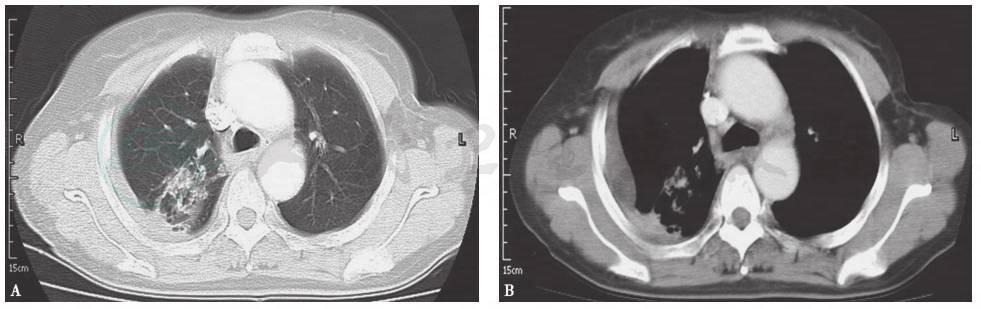

胸部CT:两肺门及纵隔内多个淋巴结肿大,斜裂胸膜区多发小结节,两肺间质纹理增多,双侧胸腔积液,右侧胸腔积液较前明显增多(图8)。

图8 胸部CT表现

图13 治疗7周后复查胸部CT表现

胸部CT显示纵隔淋巴结明显缩小,胸腔积液明显吸收